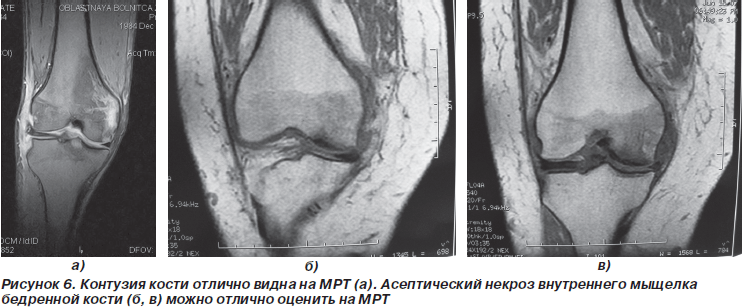

У 2 больных при МРТ были выявлены участки контузии наружного мыщелка бедренной кости, что не визуализировалось при артроскопии.

Асептический некроз мыщелков при помощи МРТ удавалось диагностировать намного раньше, чем на рентгенограмме.

Отличные результаты МРТ показала при диагностике патологии костной ткани в области коленного сустава.